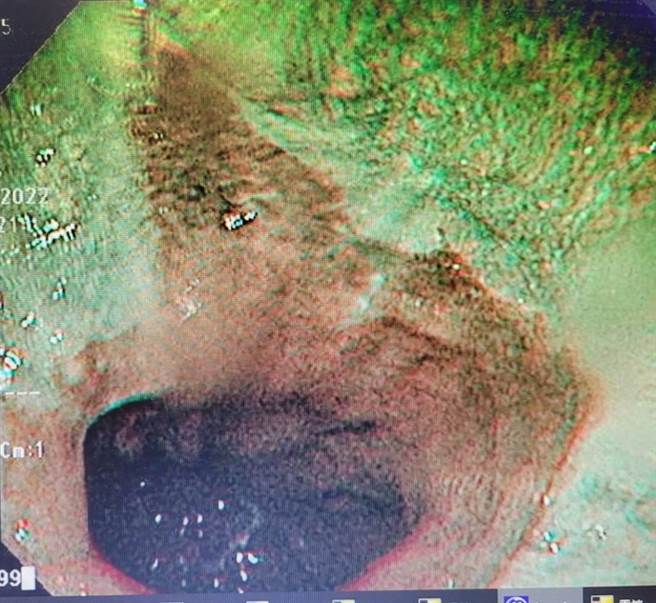

阮综合医院消化内科预防医学暨健康管理中心主任萧伟成表示,经检查江男有中度脂肪肝,业务忙碌压力大,三餐不定,也有菸酒习惯,自诉一直有胃痛、胃食道逆流,还有十二指肠溃疡。平常都上药房自行买消炎药止痛,这次连续吃五天大餐,分泌过多的胃酸像土石流一般衝垮薄弱的胃黏膜。

萧伟成指出,胃病最常发生在热爱「吃到饱」民眾的身上,若又加上边吃边说话、量多、食速快的坏习惯,就容易发生胀气、胃闷、消化不良,形成胃食道逆流。摄取过量高油高糖高胆固醇食物更容易造成肥胖、脂肪肝,也会让有「三高」体质的人上火,累积这些问题,更有造成中风的危险。